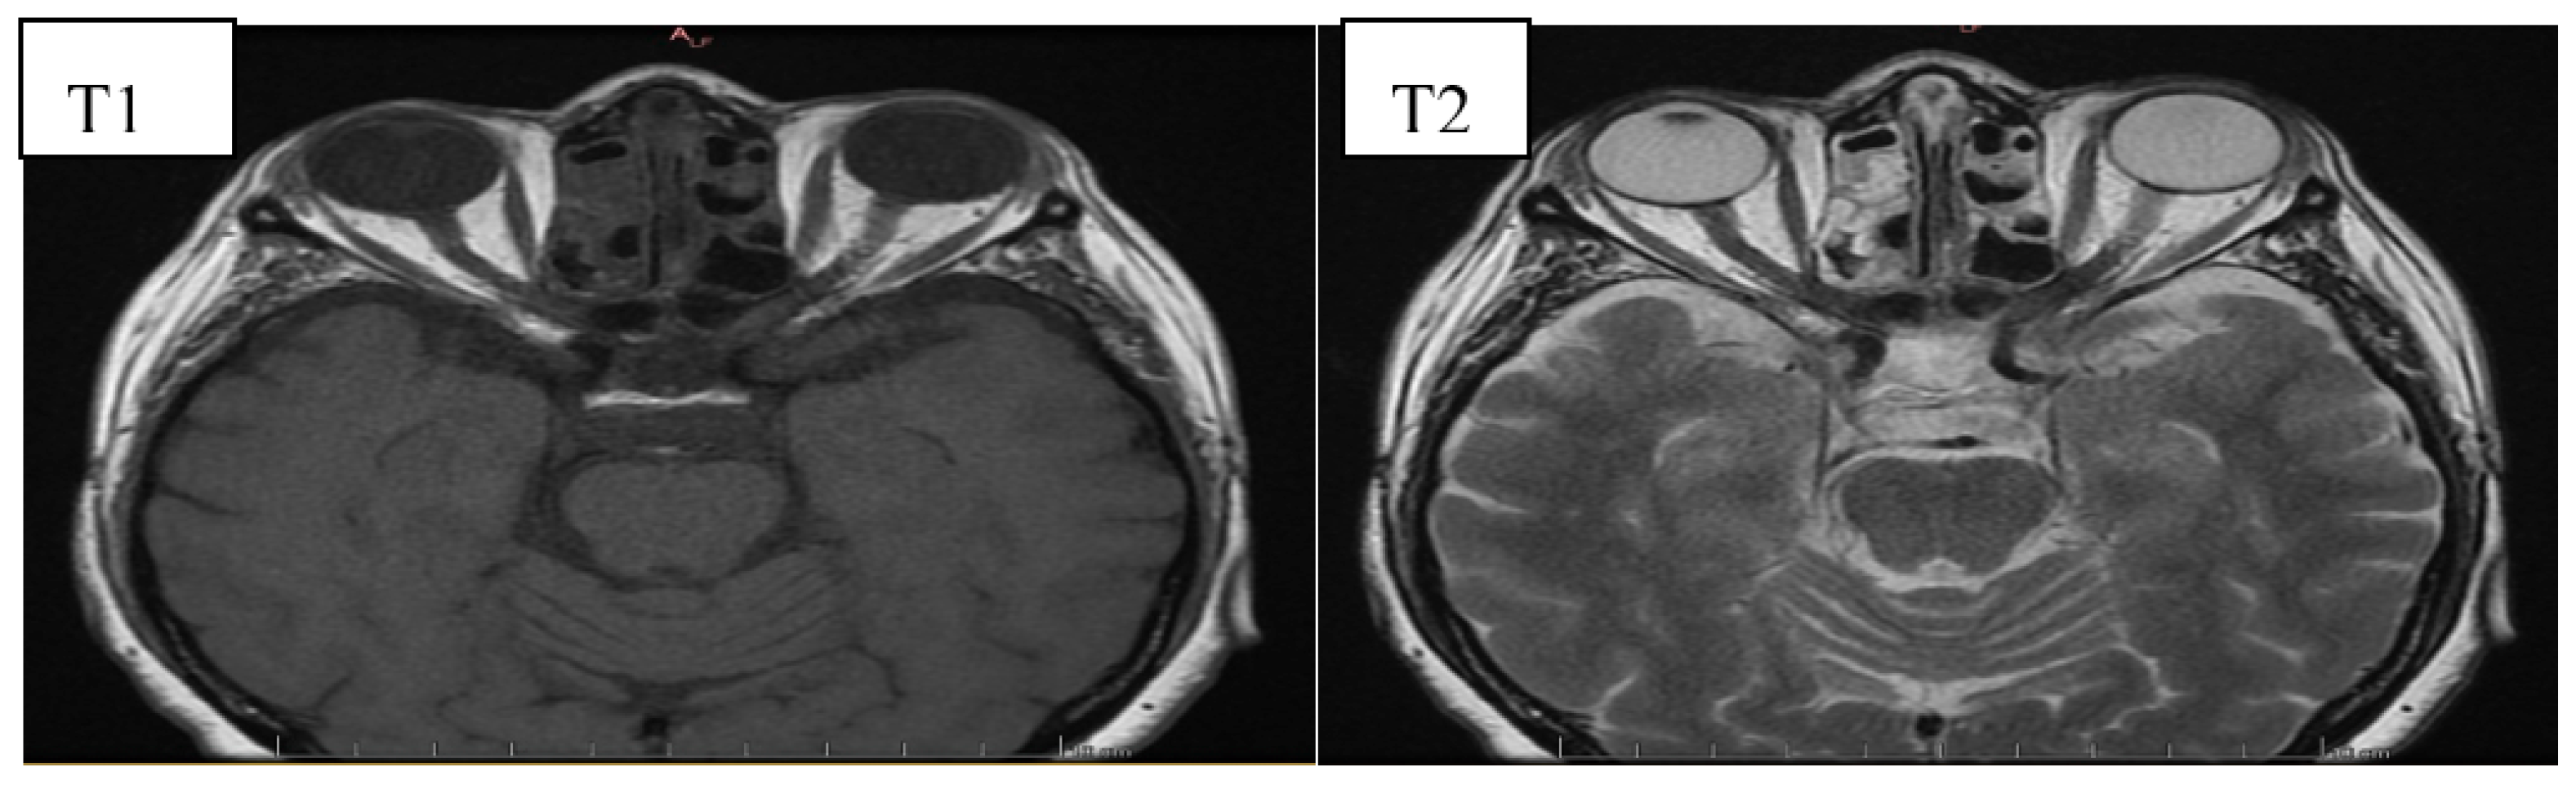

6. Image Evaluation

- Gonçalves, A.C.P.; Gebrim, E.M.M.S.; Monteiro, M.L.R. Imaging studies for diagnosing Graves’ orbitopathy and dysthyroid optic neuropathy. Clinics 2012, 67, 1327–1334. [Google Scholar] [CrossRef]

- Kahaly, G.J. Imaging in thyroid-associated orbitopathy. Eur. J. Endocrinol. 2001, 145, 107–118. [Google Scholar] [CrossRef]

- Müller-Forell, W.; Kahaly, G.J. Neuroimaging of Graves’ orbitopathy. Best Pract. Res. Clin. Endocrinol. Metab. 2012, 26, 259–271. [Google Scholar] [CrossRef] [PubMed]

- Cakirer, S.; Cakirer, D.; Basak, M.; Durmaz, S.; Altuntas, Y.; Yigit, U. Evaluation of extraocular muscles in the edematous phase of Graves ophthalmopathy on contrast-enhanced fat-suppressed magnetic resonance imaging. J. Comput. Assist. Tomogr. 2004, 28, 80–86. [Google Scholar] [CrossRef]

- Kirsch, E.; Hammer, B. Graves’orbitopathy: Current imaging procedures. Swiss Med. Wkly. 2009, 139, 618–623. [Google Scholar]